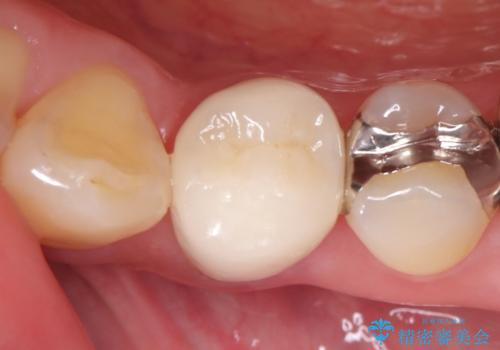

銀歯の下に虫歯 〈オールセラミッククラウン〉

- 初診時に金属の下に虫歯があることを指摘しました。もともとの詰め物の形と虫歯の大きさから被せものでの治療となりました。見た目、材質の説明をし、セラミッククラウンでの修復となりました。

- 132,000円費用は治療当時の料金となります

メタルインレーが入っていたこと、う蝕が大きかったこと、頬側にHysに対してのCRがあったことを踏まえてクラウンでの修復を選択しました。